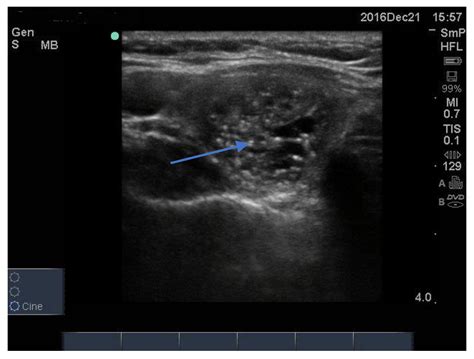

• Ultrasound: This imaging test uses sound waves to create detailed images of the thyroid gland, helping to identify the presence and characteristics of the cyst.

• Fine-Needle Aspiration (FNA): This procedure involves inserting a thin needle into the cyst to withdraw a sample of the fluid for analysis. This can help confirm the diagnosis and rule out any malignant conditions.